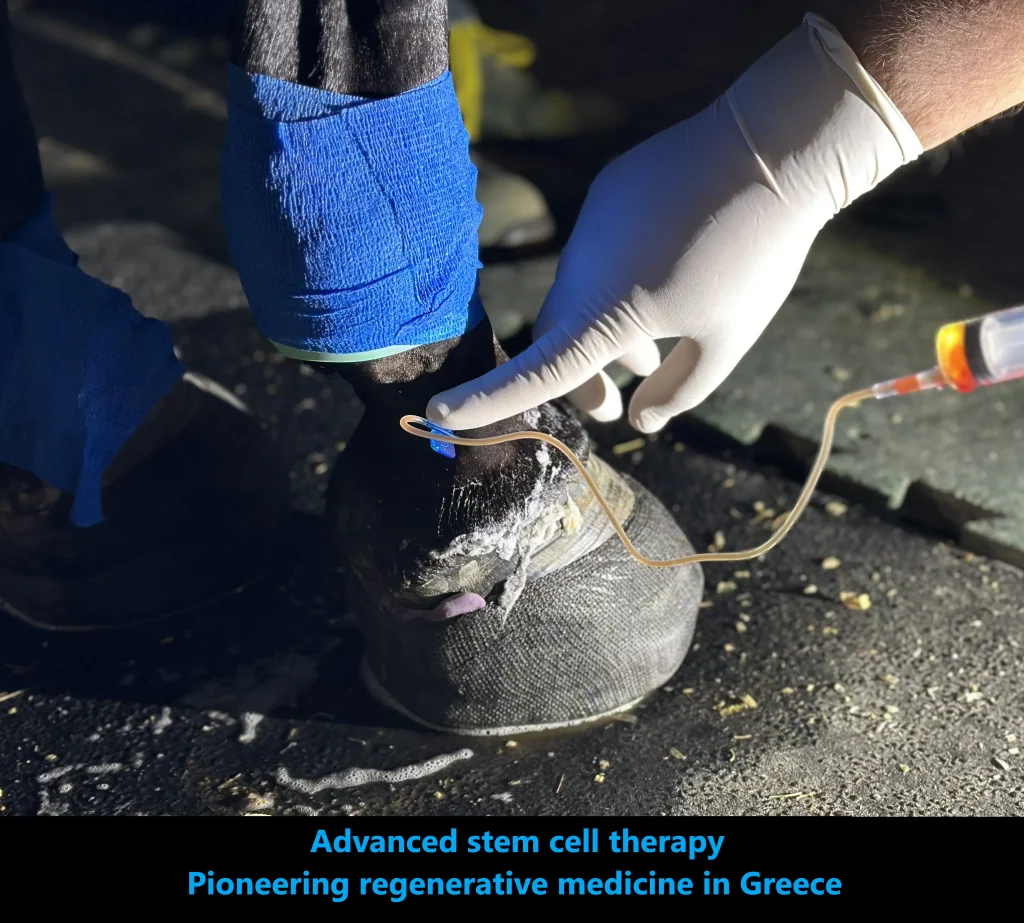

✓ Stem Cell Therapy

Used as an adjunctive treatment, stem cells have shown promising clinical results in selected laminitic patients.

- Morrison, S., Dryden, V.C., Bras, R., Morrell, S. How to Use Stem Cells in Clinical Laminitis Cases.